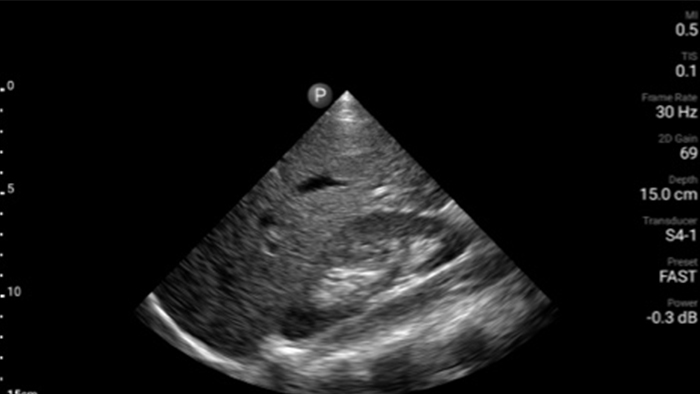

Los pacientes que sufren un ataque cardíaco necesitan atención inmediata. Los ajustes cardíacos preestablecidos de Lumify pueden ayudar a los pacientes a ser diagnosticados más rápido para mejorar sus resultados.

• Rango extendido de frecuencias de operación de 4 a 1 MHz • 2D, Doppler a color, Modalidad M, XRES avanzado e imágenes armónicas multivariables • Imágenes de alta resolución para aplicaciones abdominales y cardíacas: las optimizaciones de preajustes de imágenes cardíacas, gineco-obstétricas, pulmonares, abdominales y FAST de Lumify ayudan a la tecnología que salva vidas en entornos prehospitalarios

Lumify ayuda a la tecnología que salva vidas en entornos prehospitalarios